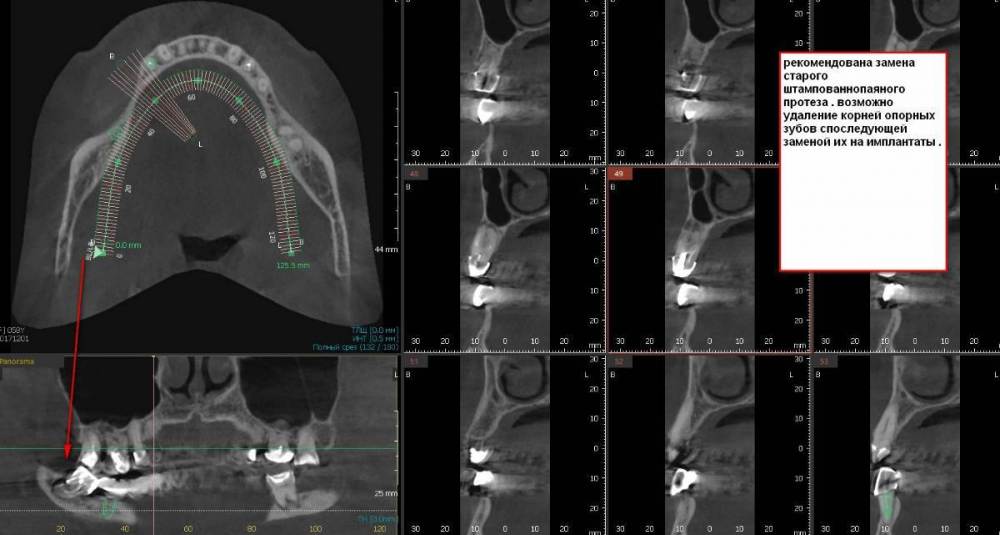

Вот с такой ситуацией обратилась к врачу, болел зуб мудрости.  Далее был сделан снимок (прилагаю фото решений- удаление опорных зубов с последующей заменой имплантами). PX20171201_162103_0000_000000FF.thumb.jpg.8c974cf49da3bb77db059abb91c7264c.jpg2018-01-24_013834.thumb.jpg.48a661d2a2f2d78a18d7b2906252d0a3.jpg2018-01-24_014845.thumb.jpg.0665ffa758959ace3ce9d7a8ff27421f.jpgпосле проведенных манипуляции появилась парастезия тройничного нерва, считаю это последствиями неверно установленного импланта, справедливо ли мое мнение?  Прохожу длительное лечение у невропатолога.  На крайнем визите врач отказал в помощи с этой проблемой и с обнаженным имплантом. (Прикладываю фото) 786267296_09_12_21.thumb.jpg.f332c30c240cb1ba19d2341b4f6014f1.jpg20220116_233530.thumb.jpg.c9cc82f18d25e9a905a2b7b1dc13eb8c.jpg20220116_232905.thumb.jpg.c3953c0b472c6e3ce1f46272ef507d2e.jpg1915694342_WhatsAppImage2022-08-20at19_39_20.thumb.jpeg.2099829af18d4d8c448126d5f323605f.jpegУ меня следующий вопрос:  верно ли назначенное лечение и насколько корректно установлены импланты, а также имелись ли противопоказания для установки имплантов, имея ввиду, что была убыль кости? Можно ли устанавливать импланты в таком случае?  прикладываю фото уже удаленного установленного на на импланты моста, правильно ли выполнен технически? (импланты пришлось удалить, а мост снять, чтобы сделать операцию по восстановлению кости, но уже в другой клинике. так как, как я писала выше, врач, установивший импланты отказал в помощи).